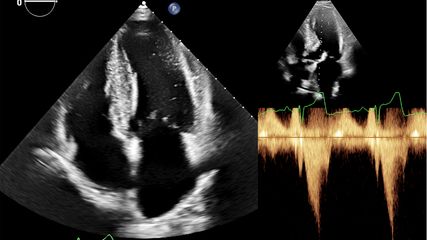

HOCM-Therapie: 6-Minuten-Gehstrecke als praktischer Marker für Therapieerfolg

Real-World-Daten sprechen für die frühe Wirksamkeit und Sicherheit von Mavacamtenin der Behandlung der symptomatischen hypertrophen obstruktiven Kardiomyopathie (HOCM). Eine kleine ...